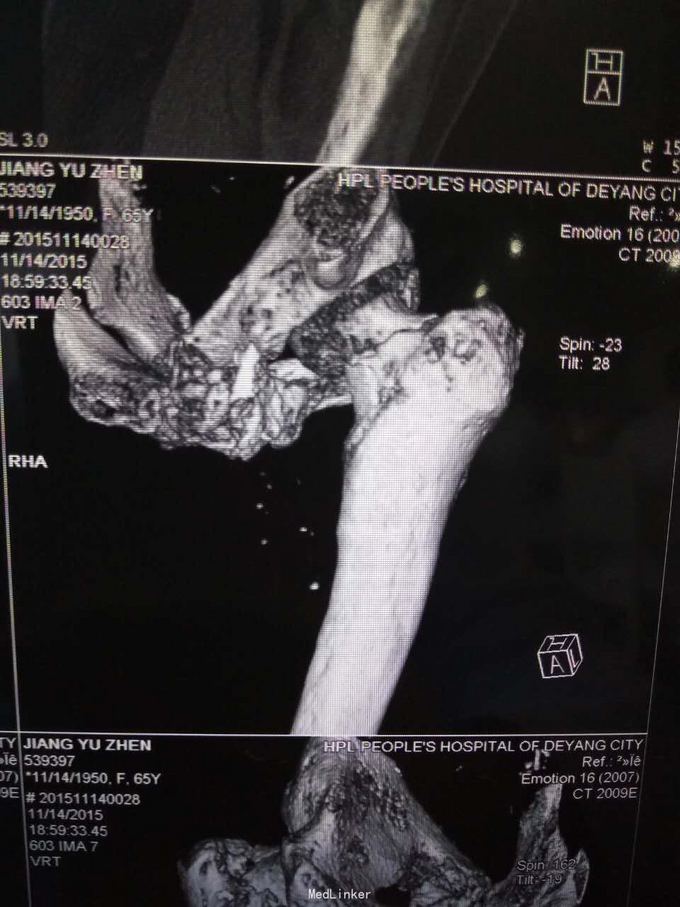

主诉:摔伤致左髋部疼痛及活动受限1小时; 病史:1小时前患者不慎摔伤,致左款疼痛,活动受限。无开放性伤口。患者半年前于华西诊断重度骨质疏松症,长期注射鲑降钙素,密固达一次。

查体,左下肢外旋畸形,髋部压痛,轴向叩击痛。 x片提示:左股骨颈、转子间骨折,左股骨耻骨上支,耻骨联合、下肢粉碎性骨折。

诊断:左股骨颈、转子间粉碎性骨折,左耻骨上支、耻骨联合、下支粉碎性骨折,重度骨质疏松症, 处理:患肢制动,牵引,注射鲑降钙素,科室讨论意见为行髋关节置换术,与换方沟通后,换方表示拒绝手术治疗,主动出院。